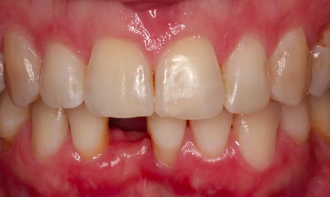

CLINICAL VIDEO Staged Horizontal GBR and Soft Tissue Augmentation for Anterior S

CAT# CV-083

Staged Horizontal GBR and Soft Tissue Augmentation for Anterior Single Tooth Implant Therapy

Dr. Sascha A. Jovanovic

CLINICAL VIDEO Single Tooth Esthetic Implant Replacement - From Diagno

CAT# CV-080

Single Tooth Esthetic Implant Replacement - From Diagnosis to Surgery to Final Restoration

Dr. Francesco Mintrone